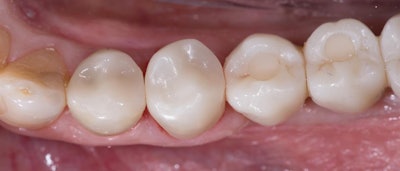

Once the Katana STML crown was prepolished (figure 4, below), sintered, and microetched, it was tried back in the mouth to verify proper contacts and occlusion. After the try-in, Katana cleaner (Kuraray Noritake) was used to clean the intaglio of the crown. This is very easy to do. Simply scrub the cleaner onto the intaglio surface of the restoration for 10 seconds or more and then rinse and dry. The purpose of the cleaner is to reinforce and enhance the bond strength after contamination during the try-in due to saliva, blood, gingival fluid, water, etc. If you choose to use it, Katana cleaner replaces having to use phosphoric etch or other cleaning products.

The final restoration blended seamlessly amongst the neighboring teeth and restorations (figure 5, below). The patient expressed his gratitude and appreciation for the appearance of his new crown and the convenience of having it fabricated and delivered in a single visit.